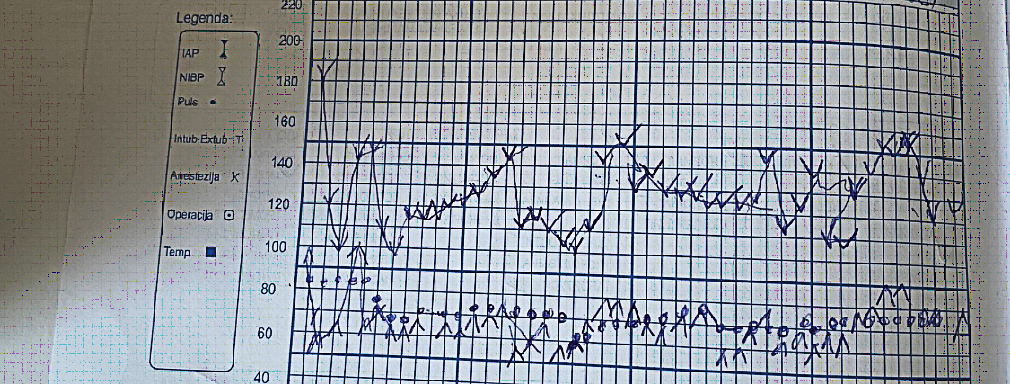

During the induction we gave Midazolam 2mg, fentanyl 0.05mg, propofol 160mg, 2% lidocaine 40mg, rocuronium 50mg. During the intervention we had two syringe pumps for our total intravenous anesthesia – TIVA, propofol 400mg/50ml/5-10ml/h, remifentanil 2mg/40ml/5-10ml/h. Fentanyl was added according to vital signs as well as a non-depolarizing myorelaxant. The patient received 1700ml NaCl 0.9% Physiological Saline, 1000ml Ringer’s, 500ml plasma expander HES 6%, 350ml transfusions of deplasmatized erythrocytes. The operation lasted 4 hours. During the operative period the patient was stable. On Figure 1 we can see the values of blood pressure and heart rate intraoperatively. Antibiotic, analgetic, gastroprotective, antiemetic therapy was given.

Figure 1. Systolic pressure is noted with the port facing up, diastolic pressure is noted with the port facing down, pulse is noted with a dot. One square indicates a 5-minute interval.